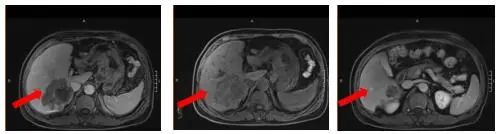

腹部增强MRI:胃壁增厚并腹腔内多发肿大淋巴结(较大者直径约2.6cm),考虑胃Ca并淋巴结转移;肝内多发异常信号灶,考虑转移瘤,6.4*7.8cm。

图1 腹部增强MRI